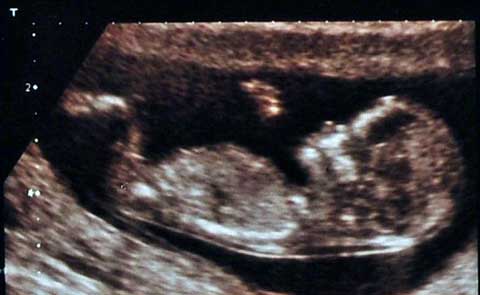

Vài giờ sau khi cô Karen Smith quan hệ với chồng trong lúc cô đang mang thai được 31 tuần, Karen đã bị chảy máu và liên tục bị chuột rút.

Các bác sĩ đã buộc phải phẫu thuật cắt bỏ tử cung khi thai nhi được 31 tần để cứu mẹ

Đầu tiên các bác sỹ cho rằng những biểu hiện của cô chỉ là bình thường, nhưng sau vài giờ sau, các bác sĩ đã thông báo họ buộc phải bỏ bào thai cô đang mang khi thực hiện thủ thuật cắt bỏ tử cung để bảo vệ tính mạng cho cô.

Thực tế là do tác động quá mạnh trong khi quan hệ với chồng đã khiến cho cô bị đứt nhau thai nên các bác sĩ buộc phải cắt bỏ tử cung để bảo vệ tính mạng cho cô. Các bác sĩ cho biết, quan hệ trong quá trình mang thai là hoàn toàn an toàn. Đối với những thai phụ bình thường thì việc quan hệ không hề liên quan tới việc sẩy thai.

Đối với trường hợp của Karen, lý do đứa con trai của cô chưa kịp chào đời đã phải từ giã cõi đời là do cô bị mắc chứng đứt nhau thai. Sau khi tai nạn đáng tiếc này sảy ra, Karen đã mất một thời gian rất lâu sống trong những đau khổ và dằn vặt chính bản thân.

Chứng bong nhau non sảy ra khi thai phụ bị chảy máu gần nhau thai, hoặc giữa nhau thai và thành tử cung.Có thể đó chỉ là một lượng máu rất ít nhưng nếu bị chảy máu nhiều đây là dấu hiệu cảnh báo nhau thai đã bị đứt hoặc bong ra khỏi lớp niêm mạc của tử cung.

Chứng bong nhau non rất nguy hiểm đối với tính mạng của cả mẹ và con – lượng máu chảy ra càng lớn sẽ lấy đi oxy và chất dinh dưỡng của bào thai.

Ngoài ra, chứng bệnh này còn làm tăng nguy cơ sinh non và bào thai sẽ gặp phải những vấn đề trong quá trình phát triển, thai chết lưu hoặc nếu có thể chào đời thì em bé cũng chỉ có thể sống được một khoảng thời gian rất ngắn.

Các trường hợp thai phụ bị bong nhau non là không phổ biến chỉ có khoảng 1 ca trong số 50 người mang thai. Thông thường hiện tượng bong nhau non thường xảy ra ở cuối thai kỳ hoặc trong quá trình lâm bồn.

Name:	hinh-anh-sieu-am-khi-thai-nhi-duoc-17-tuan.jpg